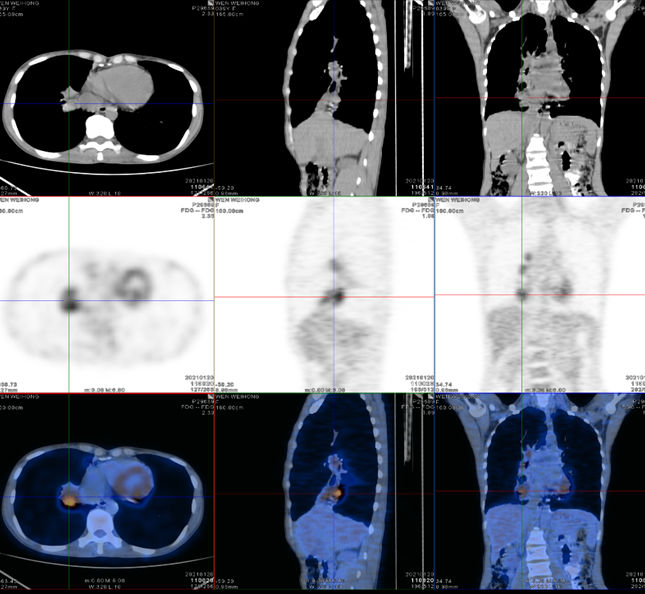

图5 患者PET-CT结果

讨论五:

患者PET-CT显示右下叶纵隔旁一块影,SUV>2.5,如何排除肿瘤或真菌感染合并肿瘤?

专家讨论

Doctor X:这一位置做肺活检确实有难度,我的建议是先治疗ABPA,然后继续观察病灶的变化,如果病灶不能缩小或进一步增大,再想办法做穿刺。